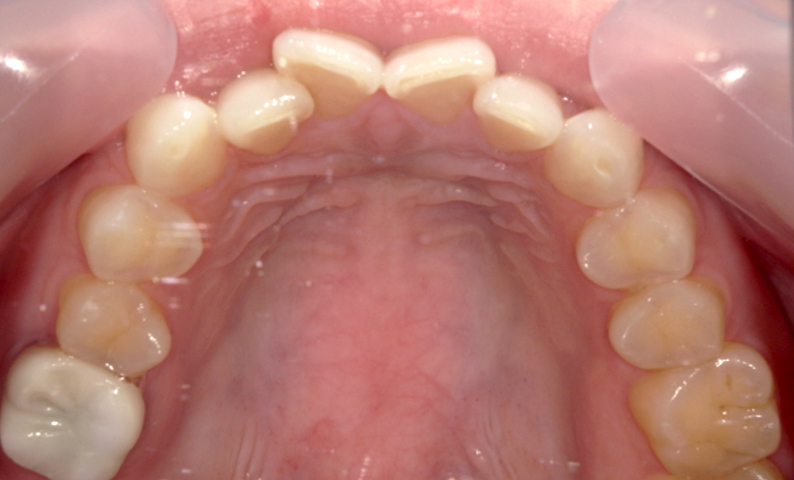

症例_003 前歯「八の字/V字型」症例

治療期間:8ヶ月金額:30万円+税30代女性八の字/V字型上の前歯だけ

| Before | After |